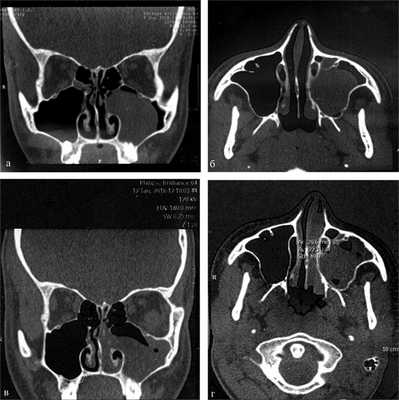

Больной Ф., 17 лет, поступил в ЛОР-клинику в январе 2016 г. по поводу отсутствия дыхания через левую половину носа, ринореи, постназального затека. Считает себя больным в течение 6 мес. В сентябре 2015 г. обращался с подобными жалобами к оториноларингологу, однако при осмотре в полости носа патологических изменений не выявлено; на СКТ от 09.09.2015 была обнаружена киста левой верхнечелюстной пазухи (рис. 2, а, б).

Рис. 2. СК-томограмма больного Ф. а, б — СКТ от 09.09.2015: определяется киста левой верхнечелюстной пазухи, полость носа свободна; в, г — СКТ от 12.01.2016: имеется киста и АХП.

В январе 2016 г. при проведении передней риноскопии и эндоскопического исследования у больного обнаружен АХП слева. На СКТ околоносовых пазух от 12.01.2016 выявлен АХП, исходящий из левой верхнечелюстной пазухи (см. рис. 2, в, г). Полип был удален эндоскопически.

Данный случай интересен тем, что нам удалось документировать срок, в течение которого полип распространился из верхнечелюстной пазухи в полость носа, а затем и в хоану. Для этого потребовалось 4 мес.